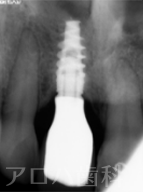

CASE01/50代男性

初診時

治療終了後5年時

| 主訴 | 左の奥歯が噛めない |

|---|---|

| 治療内容 | 下顎臼歯3歯欠損をインプラントで修復しました。 デジタル機器を使いコンピュータで理想的な歯の形態を設計。 歯ぐきに隙間が出来る事なく修復できました。 |

| 治療期間 | 3ヶ月 |

| 治療費用 | 1,375,000円 |

| 費用詳細 | ・サージカルガイド 55,000円 ・GBR 110,000円 ・インプラント手術+アバットメント+上部構造(3歯) 1,320,000円 |